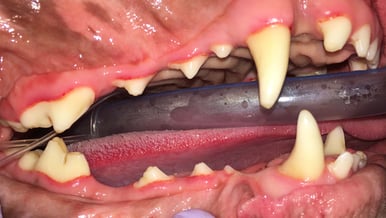

Below: Overview before procedure: (left and right)

%20-%20March%202024/Overview%20of%20right%20side%20before%20dental%20cleaning.jpg?width=386&height=240&name=Overview%20of%20right%20side%20before%20dental%20cleaning.jpg)

Below: Overview after procedure: (left and right)

. %20-%20March%202024/Overview%20of%20right%20side%20after%20dental%20cleaning.jpg?width=386&height=219&name=Overview%20of%20right%20side%20after%20dental%20cleaning.jpg)

Below: (left) Close up of non-vital 204 before RCT (right) Close up of non-vital 204 after RCT

*Note that performing root canal therapy cannot remove all of the staining located in the dentinal tubules.